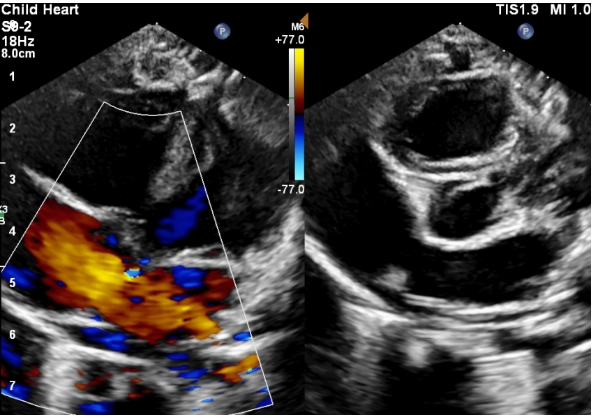

在赵源主任医师的耐心解释和坚持下,欣欣妈妈最终还是带宝宝来到超声医学科进行了心脏彩超检查,检查发现:先天性心脏病 房间隔缺损(继发孔型)(如下图)。

赵源主任医师介绍,如今很多宝宝经常反复得肺炎,如果听诊发现可疑情况,我们一般也会让患儿做个心脏彩超检查,发现宝宝频繁得肺炎的元凶就是先天性心脏病中的房间隔缺损(简称“房缺”)。

目前绝大多数房缺根据临床表现及超声心动图即可确诊。心脏彩超检查是目前最简单直接的无创检查手段,可以发现房间隔缺损的类型、位置以及大小。并可以测量肺动脉压力评估有无肺动脉高压,评估右心的大小及功能。